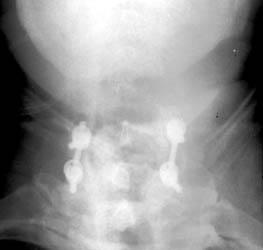

3 months later, follow-up films show the posterior fixation at C6-7. Now noted that the screw at C7 has slipped off the support rod on the right.